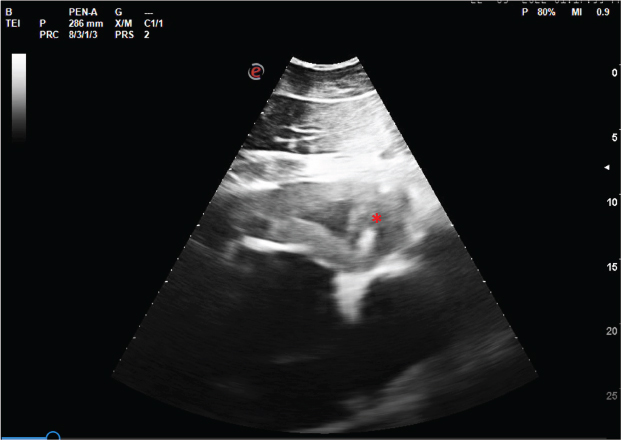

The mare returned on the 22nd of September with prostration, fever, dyspnoea, lack of appetite, severe weight loss, dehydration, and pronounced oedema and lymphadenopathy of the head. At physical examination, increased capillary refill time (3 seconds), tachycardia (72 bpm), and tachypnoea (32 rpm) were noted. There was no positive jugular pulse and intestinal motility was greatly diminished. Abdominal ultrasound and rectal palpation ruled out colic. At this point, haematology and biochemistry revealed severe thrombocytopenia with alterations in most biochemical parameters (decreased albumin/globulin ratio, increased urea, creatine kinase, and iron, and decreased gamma-glutamyl transferase). A fluid therapy protocol with Ringer's Lactate via IV supplemented with 2 l of colloid was implemented and the previous temperature and antibiotic therapy protocol was maintained. Despite the treatment efforts, the mare's body temperature reached peaks of 40.2°C and from then on, the mare failed to clinically respond to antipyretics. Thoracic, abdominal, and cardiac ultrasounds were performed, revealing an atypical image of the cardiac silhouette at the level of the 4–6th left intercostal spaces, characterized by an irregular border and thickening of the cardiac wall (Fig. 2). With no improvement of the clinical condition, the mare collapsed on 24th of September, and the corpse was subjected to necropsy examination.

Fig. 2. Ultrasound image of the heart showing irregular border and thickening of the left ventricle wall (*).